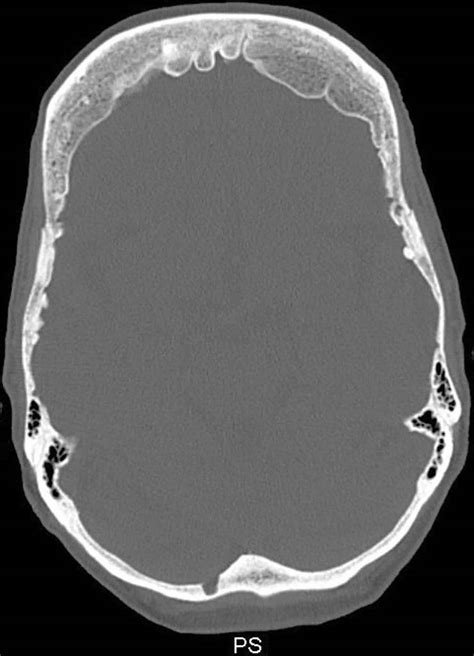

Hyperostosis frontalis interna (HFI) is a condition characterized by a benign, symmetrical thickening of the inner table of the frontal bone of the skull. While the term might sound intimidating, it is a relatively common radiological finding, often discovered incidentally during imaging scans performed for other reasons, such as headaches or minor head trauma. Understanding this condition is important for clinicians and patients alike, particularly because it can sometimes be associated with hormonal or metabolic factors, although its exact clinical significance remains a subject of ongoing research.

At its core, Hyperostosis frontalis interna manifests as bony growths—known as osteomas or nodular projections—on the inner surface of the frontal bone. Unlike malignant skull conditions, these deposits are benign and generally do not extend into the brain tissue itself. They are most frequently identified through computed tomography (CT) scans or magnetic resonance imaging (MRI) of the head.

- Imaging: A CT scan is the gold standard for visualizing bone density and structure, making it the most effective tool for confirming HFI.